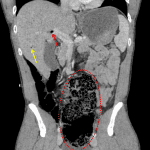

- Massively distending, medially displaced cecum with associated pneumatosis

- Gas within the ileocolic and superior mesenteric veins extending to the main portal vein and intrahepatic portal branches

- Cecal volvulus

Findings consistent with cecal volvulus and associated ischemia evidence by cecal pneumatosis and portal venous gas. No evidence of perforation. Recommend surgical consultation.